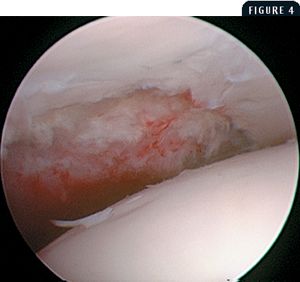

A 7-month-old intact male Labrador retriever was presented for evaluation of a two-week history of left hindlimb lameness.